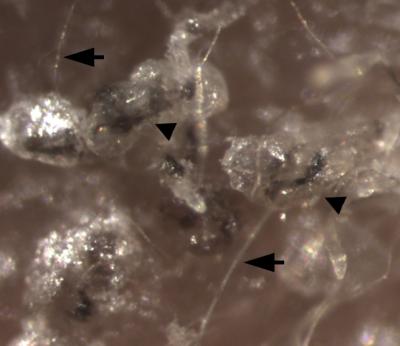

Comparison of the gene expression patterns of the human iPSC-derived epithelial stem cells with epithelial stem cells obtained from human hair follicles showed that the team had succeeded in producing the cells they set out to make in the first place. When they mixed those cells with mouse follicular inductive dermal cells and grafted them onto the skin of immunodeficient mice, they produced functional human epidermis (the outermost layers of skin cells) and follicles structurally similar to human hair follicles.